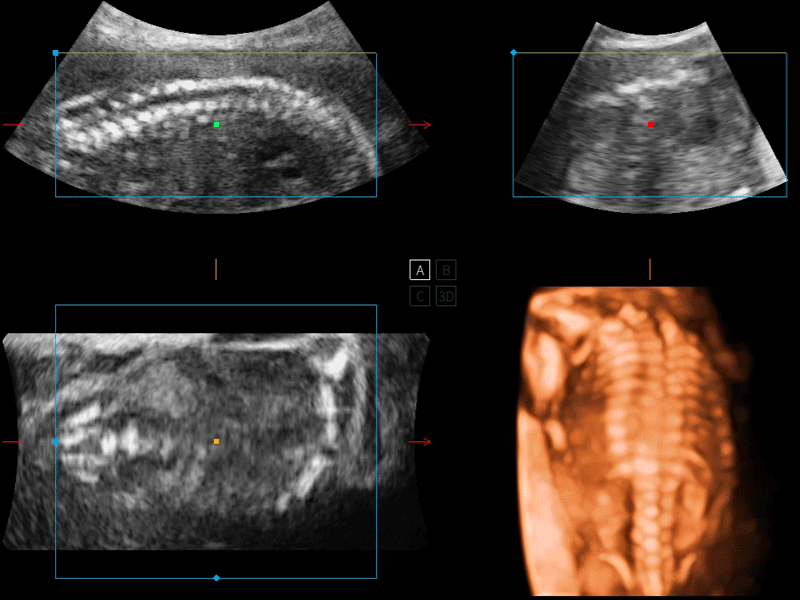

開立醫(yī)療通過不斷的技術(shù)創(chuàng)新,為大眾的生命健康提供持續(xù)關(guān)愛。P12 Plus采用全新一代超聲成像平臺,新平臺旨在將真實(shí)還原組織解剖結(jié)構(gòu)作為首要目標(biāo)。平臺采用全新集成化硬件模塊,搭載新一代芯片,系統(tǒng)性能得到大幅提升,為您的診斷提供了豐富的臨床信息。優(yōu)異的圖像表現(xiàn),豐富的探頭配置,全面的應(yīng)用功能,為您日常診斷提供了可靠的助手。

P12 Plus

彩色多普勒超聲診斷系統(tǒng)